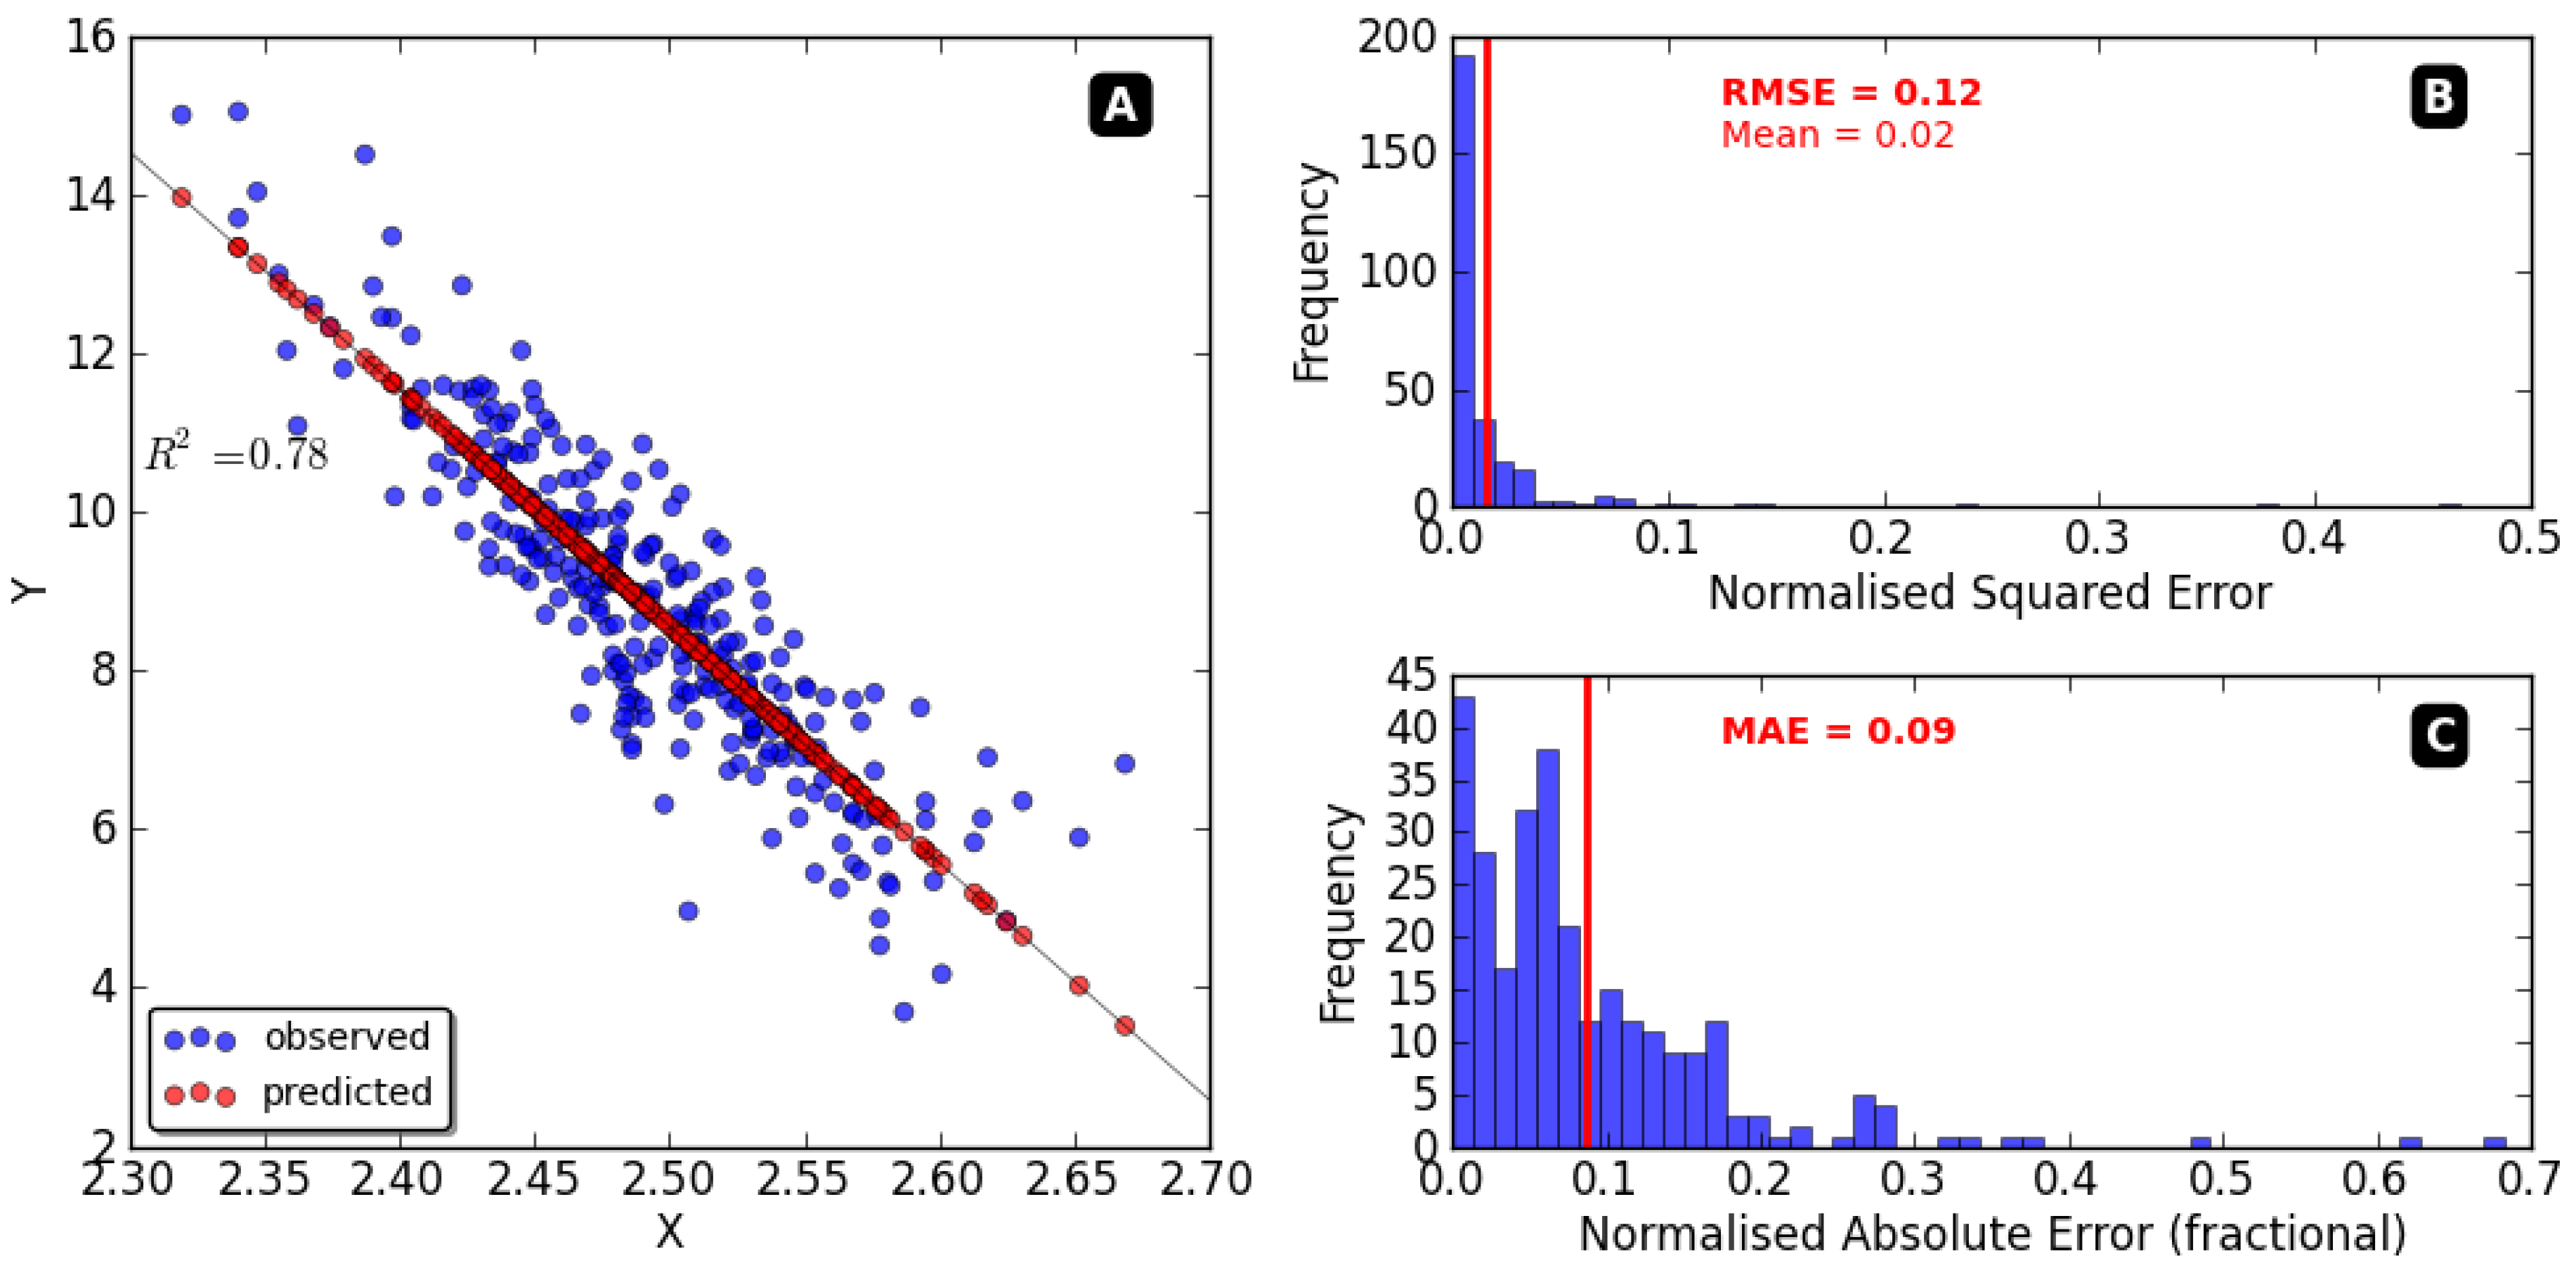

3.1. Experimental Results Analyses

3.2. Experimental Results